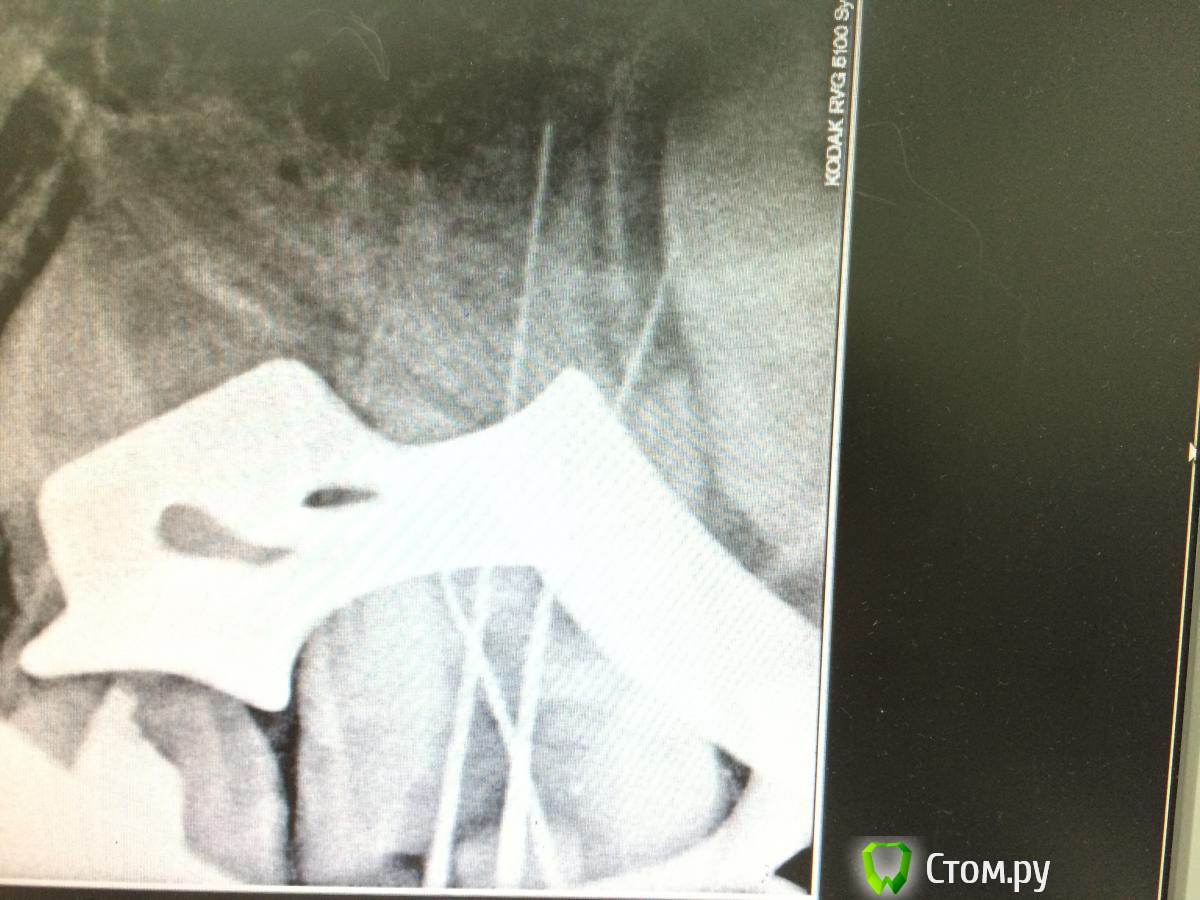

Faya Опубликовано 9 октября, 2014 Поделиться Опубликовано 9 октября, 2014 Доброго времени суток, уважаемые коллеги. Прошу поделиться опытом и мыслями в связи со следующим клиническим случаем. Обратился за помощью мальчик 8 лет - зуб 2.6 - боль, усиливающаяся при накусывании, зуб под временной пломбой. Из анамнеза - 7 суток назад в гос. поликлинике в связи с осложнением кариеса наложен мышьяк под повязку (все со слов папы), боль усиливалась, при повторном обращении вновь наложен мышьяк (вчера). Боль усиливалась...При обращении - конфигурация лица не изменена, по переходной - спокойно, перкуссия слабоболезненна, под временной пломбой, подвижность 1 степени, ИРОПЗ 0,8, разрушен под десневой край на миллиметра 2, что в принципе на мой взгляд не так существенно, т.к. предпологается увеличение клинической высоты при прорезывании (не знаю, права ли). На рентгенограмме (забыла сфотографировать, при возможности добавлю) - сообщение кариозной полости с полостью зуба, корни - раструб. Что сделано - анестезия, восстановление стенок, коффердам, удаление распада, получен гной, мед. обработка 2% хлоргексидин (парканом мыть побоялась), на устья рыхло ватный шарик с жидко замешанным пульпотеком (применяю при обострении пульпита м/з на несколько дней перед пломбированием каналов, крезофены - пульперилы в м/з и несформированных постоянных, по моему мнению, раздражают периодонт, поэтому решила использовать его) под септопак. Явка через 4 суток. Папа предупрежден о возможных осложнения и исходах, условности лечения. У кого какой был опыт в лечении таких зубов? Может какие советы-рекомендации, т. к. с подобным сталкиваюсь впервые, ранее только приходилось лечить пульпиты несформированных, вела с метапексом до окончания формирования, потом пломбировала латералкой, проблем никогда не было. Какой прогноз в данном случае? Ссылка на комментарий

Faya Опубликовано 11 октября, 2014 Автор Поделиться Опубликовано 11 октября, 2014 Rg Ссылка на комментарий

Faya Опубликовано 11 октября, 2014 Автор Поделиться Опубликовано 11 октября, 2014 Выложите снимок. добавила снимки Ссылка на комментарий